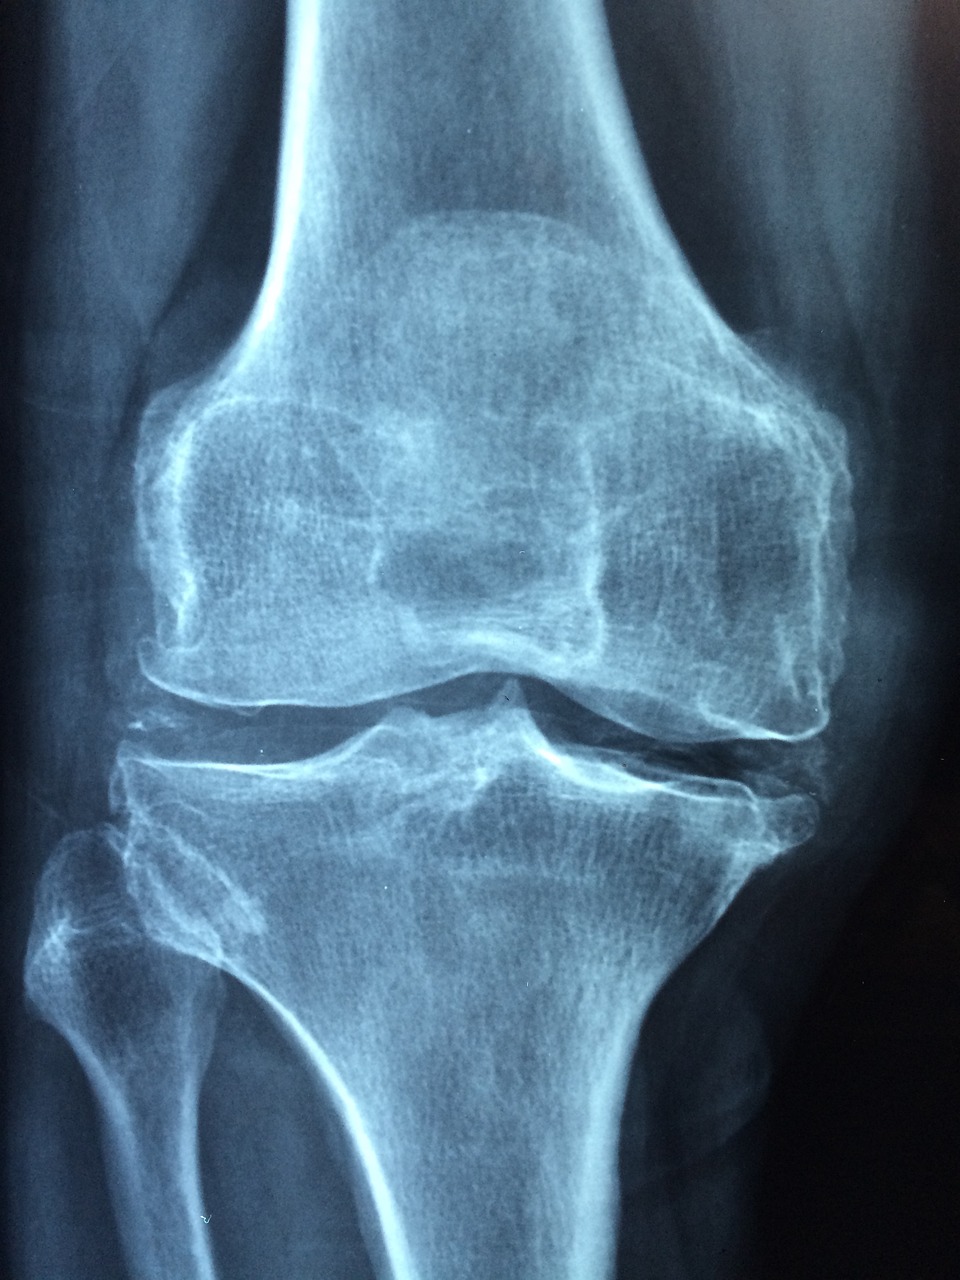

3. 진단

박리성 골관절염의 진단을 위해서는 의사의 정밀한 진찰이 필요합니다. X-레이, MRI, CT 스캔 등의 영상 진단을 통해 관절의 상태를 확인하고, 필요한 경우 관절경 검사를 통해 직접적으로 관절 내부를 관찰합니다.